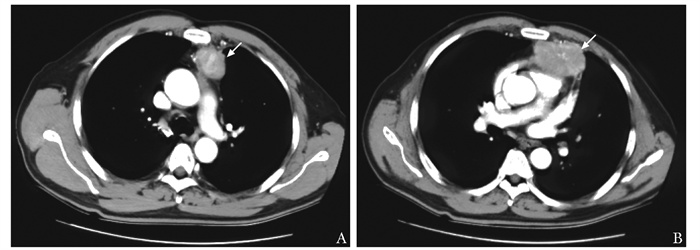

结果  患者为中年男性,是目前国内外报道的首例被诊断为胸腺原发上皮肌上皮癌的患者。该患者经手术、化疗、放疗、分子靶向治疗等综合治疗后仍出现疾病进展,从手术确诊至死亡时间为22个月。

Results  The patient was a middle-aged male diagnosed with primary EMC of the thymus, and he was the first case currently reported at home and abroad. Even though the patient received comprehensive treatments including surgery, chemotherapy, radiotherapy and molecular targeted therapy, he still experienced disease progression, with a survival time of 22 months after surgery.